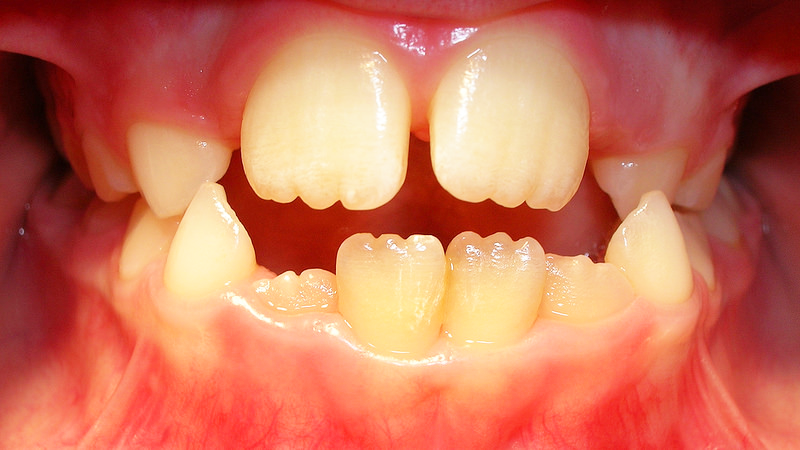

*Esto es lo que llamamos mamelones dentales. Foto tomada de www.juanbalboa.com*

¿Qué son los mamelones dentales?

Son protuberancias de esmalte y dentina (diente), que aparecen únicamente en los dientes permanentes y que son visibles una vez estos dientes erupcionan en la boca de tu hijo (a).